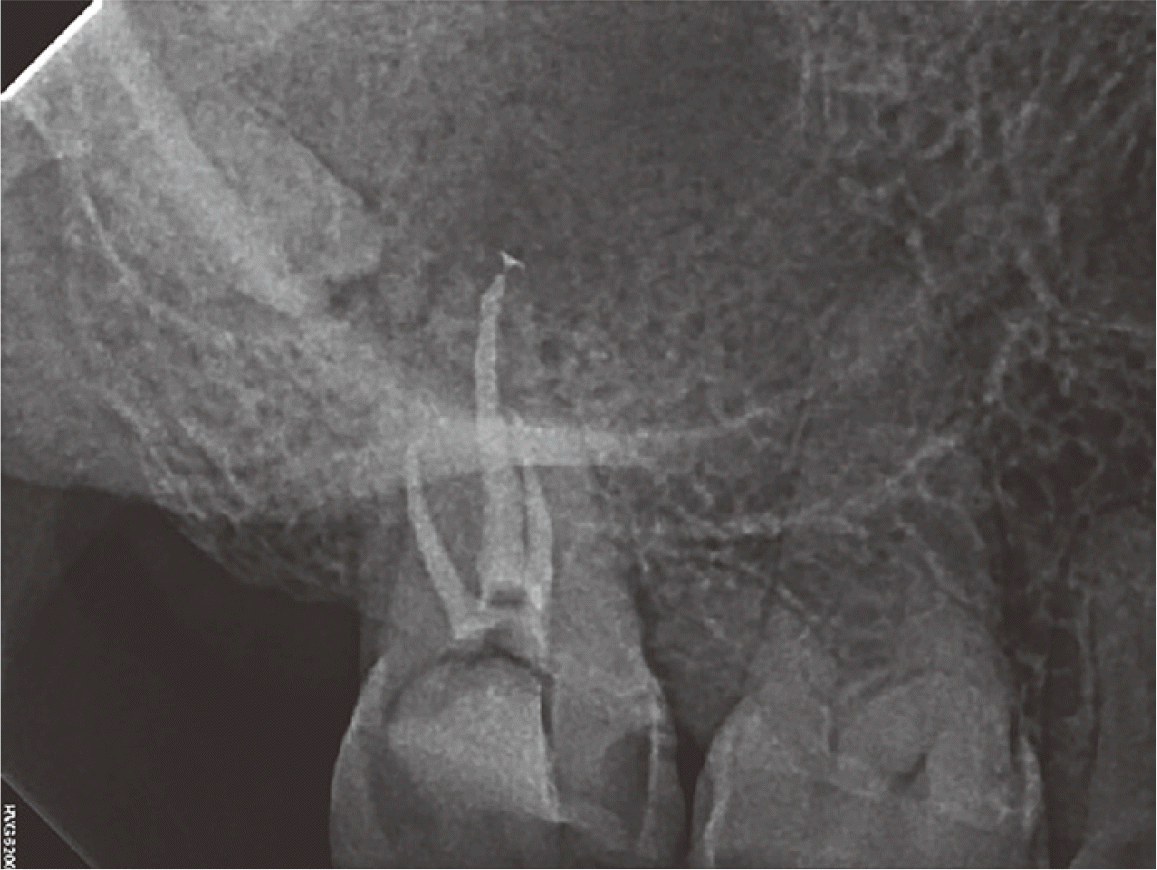

45세 여자환자가 상악 우측 어금니 부위주변 잇몸에서 고름이 나오고 코나 목으로 고름이 넘어간다는 주소로 원광대학교 대전치과병원 구강악안면외과에 내원한 뒤 상악 우측 제2대구치 평가를 위해 보존과로 의뢰되었다. 해당치아는 치수에 근접한 심한 우식 및 구개측에 sinus tract 관찰되었다(Fig 4A). 임상 검사상 타진 및 저작검사에 양성 반응 보였으며 생활력은 존재하지 않았다. CBCT 상 구개측 치근에 치근단 병변, 우측 상악동 점막 비후 및 상악동에 매우 근접한 매복된 #18 치아 관찰되었다(Fig 4B and 4C).